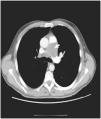

La importancia de un soplo tricuspídeo

The importance of tricuspid murmur